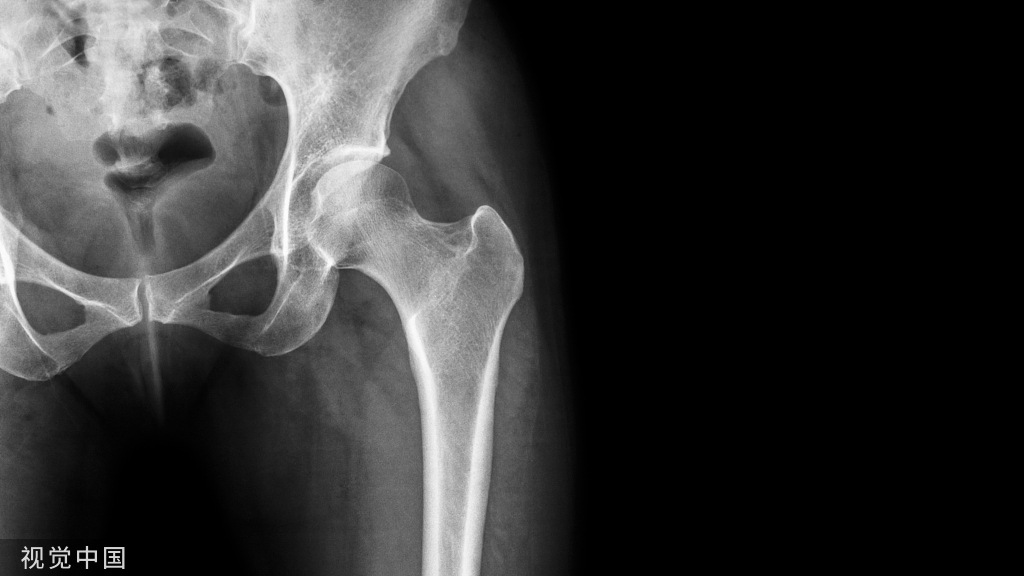

髋关节脱位是骨科常见急诊,遇到脱位一定要复位,但是复位可不是那么容易的呀,俗话说胳膊再粗掰不过大腿,今天介绍一种复位方法。

髋关节脱位主要分为后脱位和前脱位,80%都为后脱位

最常见的仪表盘类损伤常伴随后脱位,需要行X线进行脱位的确诊